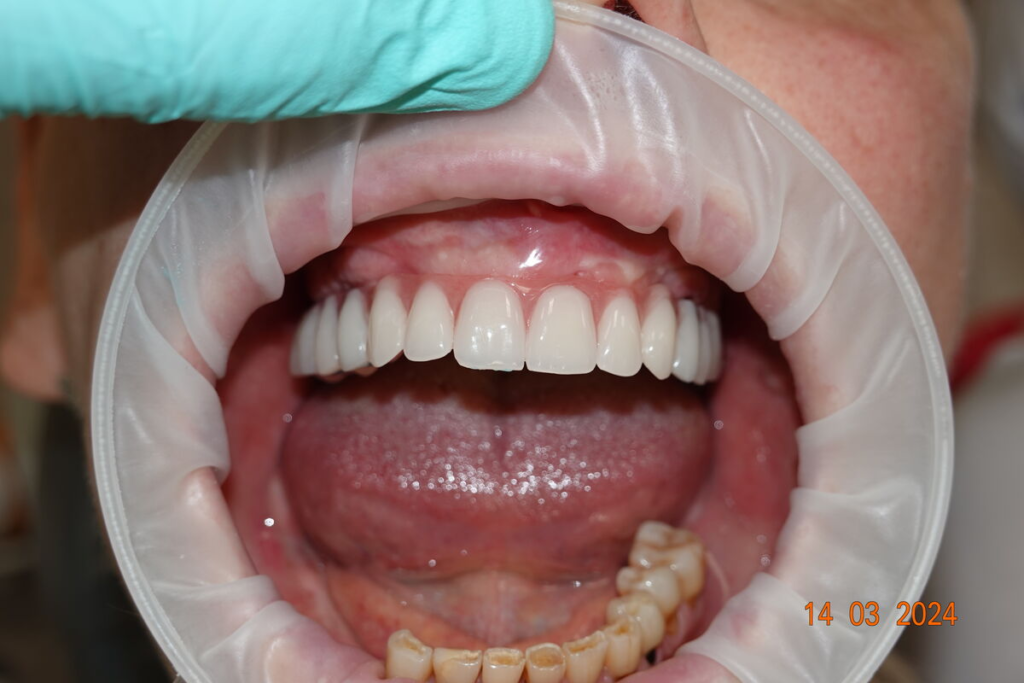

3. Nové zuby tentýž den

Odcházíte s pevnými dočasnými zuby — bez snímatelné protézy.

Můžete mluvit, smát se a jíst měkkou stravu.

Používáme multivrstvý zirkon pro maximální estetiku, pevnost a dlouhou životnost.